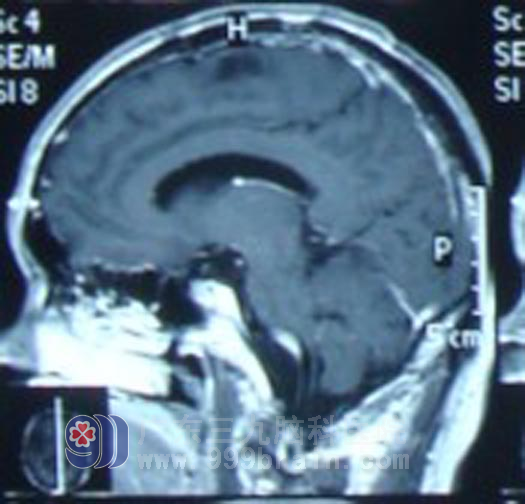

完善相关检查后,梁先生接受了左额中央区转移瘤切除术,术后病理回报是高至中分化腺癌。梁先生术后今年1月开始行全脑放疗及肺部适形放疗,后脑局部再行X刀加量治疗。放疗期间,梁先生未出现特殊不适。放疗结束后遵嘱按时行6周期静脉化疗。现梁先生一般情况良好,复查MR显示肿瘤明显缩小,得到了良好的控制。http://www.999brain.com/

头部放疗后